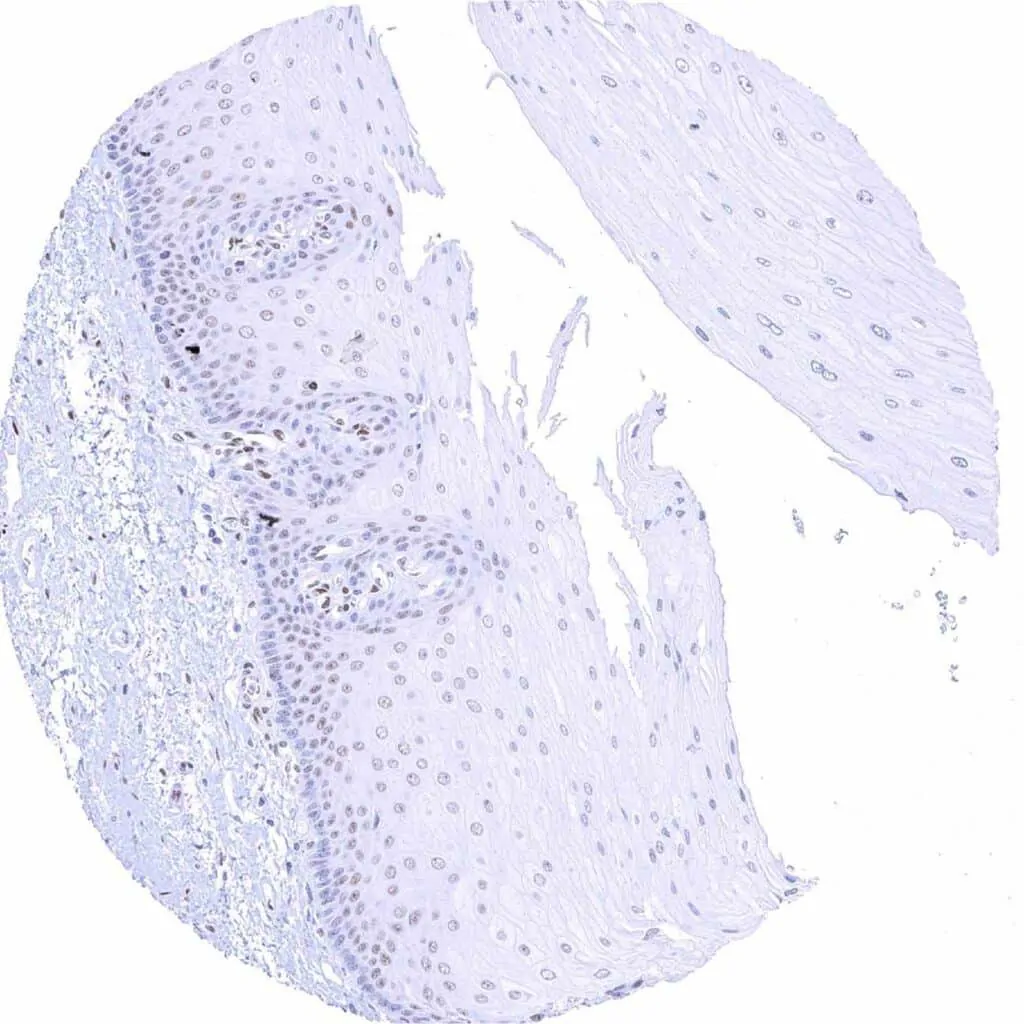

Tonsil, surface epithelium – Weak to moderate TLE1 staining of a subset of lymphocytes and of the squamous epithelium, predominantly of the suprabasal cell layers